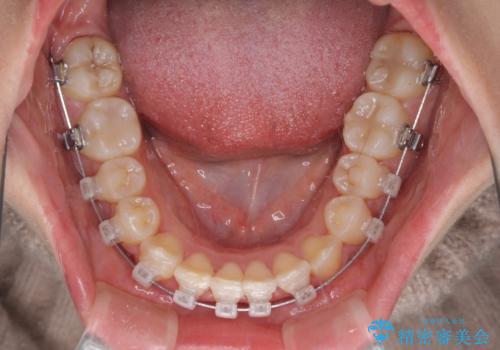

- クリアブラケット

- 上顎の八重歯と、上下前歯のデコボコを気にして来院された患者様です。

奥歯の咬み合わせを見ると、上顎臼歯が下顎に対して前方にあり、叢生改善により口元が突出する顔貌ではなかったため、上顎左右第一小臼歯2本を抜歯し、ワイヤー装置にて矯正治療を行うこととしました。